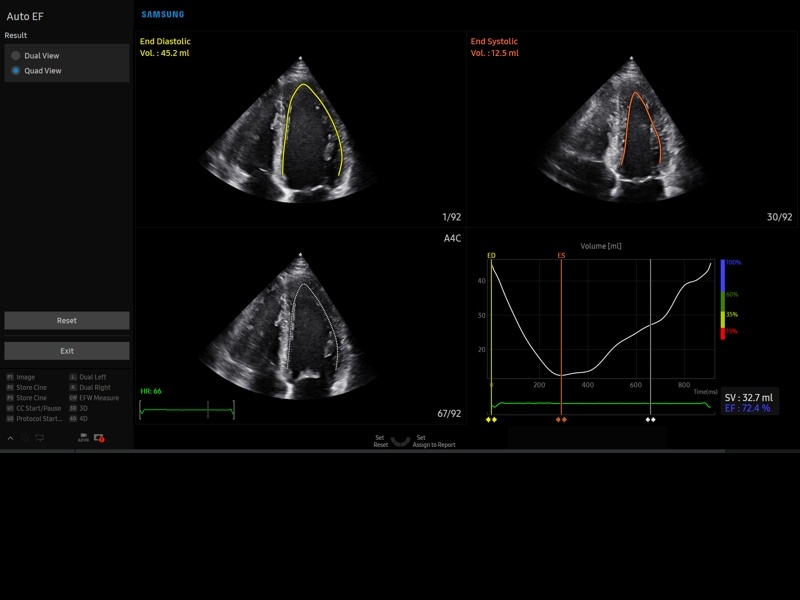

• Кардиологический пакет с функцией StressEcho

• M - одномерный режим для исследования сердца, анатомический М-режим (необходим кардиопакет), CM - цветной М-режим (необходим кардиопакет).

• Кардиопакет: тканевый допплер (TDI) + анатомический М-режим + цветной М-режим (CM) + программное обеспечение.

• МодульStrain+- программа не векторной оценки степени сократимости миокарда с выведением автоматически расчетов и графиков на экране отдельно по каждому сегменту.

• Пакет кардиологических исследований.

М-режим:измерение диаметра аорты, передне-заднего размера ЛП, толщины МЖП (систолическая и диастолическая), толщины ЗСЛЖ (систолическая и диастолическая), размеров ЛЖ и ПЖ (систолический и диастолический), ФВ (Teichholz).

B-режим:измерение диаметра аорты (восходящей, дуги, нисходящей, на уровне синусов Вальсальвы, на уровне створок аортального клапана), определение размеров ЛП и ПП (максимальный, минимальный, систолический, диастолический, переднее-задний, верхнее-нижний, медиально-латеральный), расчет объемов ЛП и ПП, объемов ЛЖ (метод "Площадь-Длина", метод дисков (Simpson)), массы миокарда ЛЖ, индекса массы миокарда ЛЖ.

CD-режим (ЦДК):измерение радиуса ПФСМР (PISA), полуколичественная оценка трансмитрального, транстрикуспидального, трансаортального и транспульмонального кровотока (оценка регургитации), оценка аномальных сбросов крови через МПП И МЖП.

PW-режим (импульсно-волновой допплер):автоматическая, полуавтоматическая и ручная трассировка допплеровского спектра митрального, аортального и трикуспидального клапанов, клапана легочной артерии, кровотока в выходном тракте ЛЖ и ПЖ (пиковая/средняя скорость, пиковый/средний градиент давления, время изоволюметрического расслабления ЛЖ, время ускорения, замедления, выброса), оценка кровотока легочных и печеночных вен.

CW-режим (постоянно-волновой допплер):программы расчета работы митрального, аортального и трикуспидального клапанов, клапана легочной артерии.

TD-режим (тканевой допплер):количественная оценка локальной сократительной функции стенок ЛЖ и ПЖ.

Сокращения:ЛП/ПП - левое/правое предсердие, МЖП - межжелудочковая перегородка, МПП - межпредсердная перегородка, ЗСЛЖ - задняя стенка левого желудочка, ЛЖ/ПЖ - левый/правый желудочек, ФВ - фракция выброса, ПФСМР - площадь формирующейся струи митральной регуритации (PISA - proximal isovelocity surface area), ПСС/КДС - пиковая систолическая / конечная диастолическая скорость.